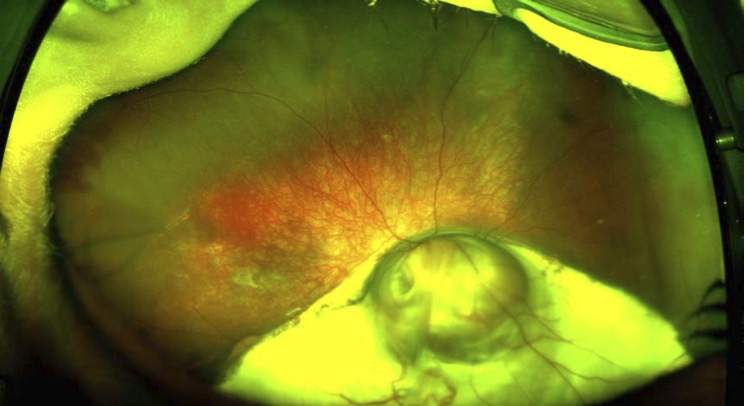

Fundal coloboma in a child as seen on RetCam wide-field retinal imaging at GOSH

Fundal coloboma — wide-field RetCam imaging, GOSH